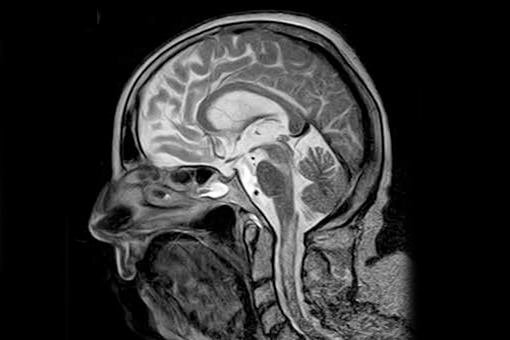

U 68-letniej pacjentki z wieloletnim wywiadem seropozytywnego RZS wystąpiły postępujące zaburzenia świadomości. Rezonans magnetyczny (MRI) mózgu i kręgosłupa szyjnego wykazał wzrost intensywności sygnału w obrazach T2-zależnych i FLAIR (fluid attenuated inversion recovery) z korespondującym ograniczeniem dyfuzji wody w DWI w konarach mózgu, moście, rdzeniu przedłużonym i szyjnym odcinku rdzenia kręgowego oraz łagodne wzmocnienie po podaniu kontrastu w prawym konarze mózgu. Rozległa diagnostyka radiologiczna i laboratoryjna, w tym przeciwciała onkoneuronalne i przeciw neuronalnym antygenom powierzchniowym, była ujemna, z wyjątkiem podwyższonego czynnika reumatoidalnego. Badanie płynu mózgowo-rdzeniowego wykazało umiarkowaną pleocytozę z przewagą komórek jednojądrzastych, nieznacznie podwyższony poziom białka, ujemne PCR w kierunku wirusów, jałowe posiewy bakteryjne, negatywną cytometrię przepływową, brak przeciwciał przeciw neuronalnym antygenom powierzchniowym.